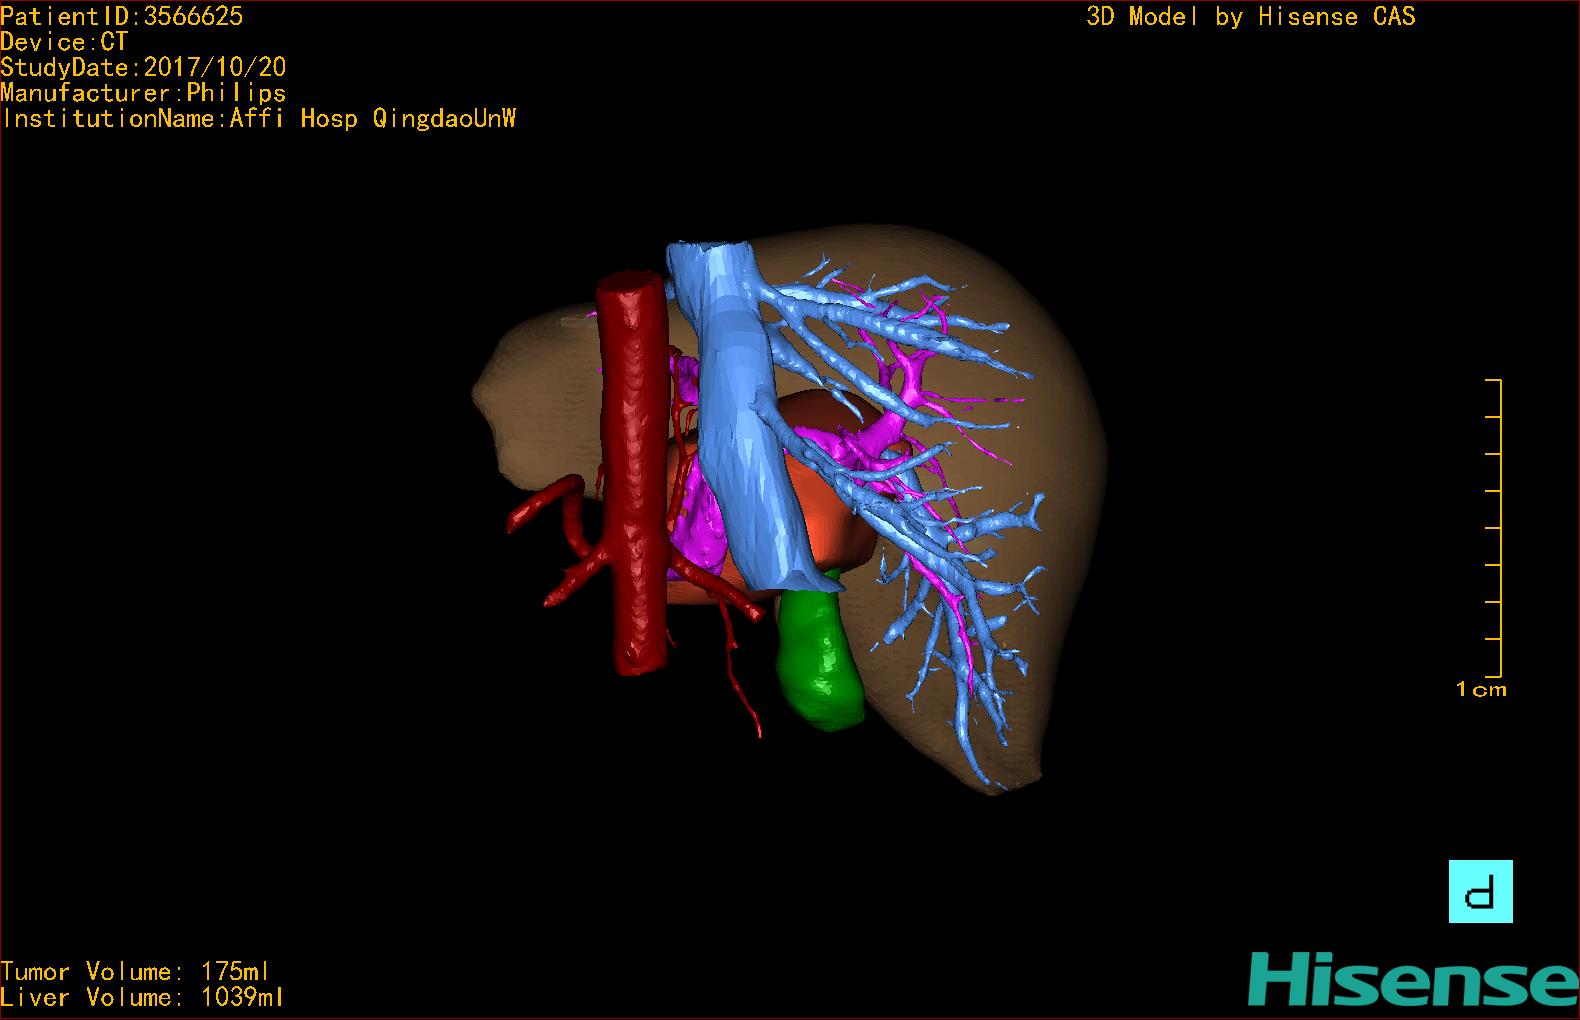

通过调节窗宽窗位调整CT序号,对肿瘤,肝实质,胆囊,下腔静脉,肿瘤,肝动脉、门静脉及肝静脉等进行三维重建;系统自动计算肿瘤体积和肝脏体积。模拟手术操作,自动计算切除肿瘤体积。肝脏体积为1039ml,肿瘤体积为175ml,通过比对40-50岁正常肝脏体积为1423.76±216.93ml,通过术前模拟手术,精准判断切除后剩余肝脏体积能耐受,避免肝衰竭发生。

术前三维重建:

重建图片